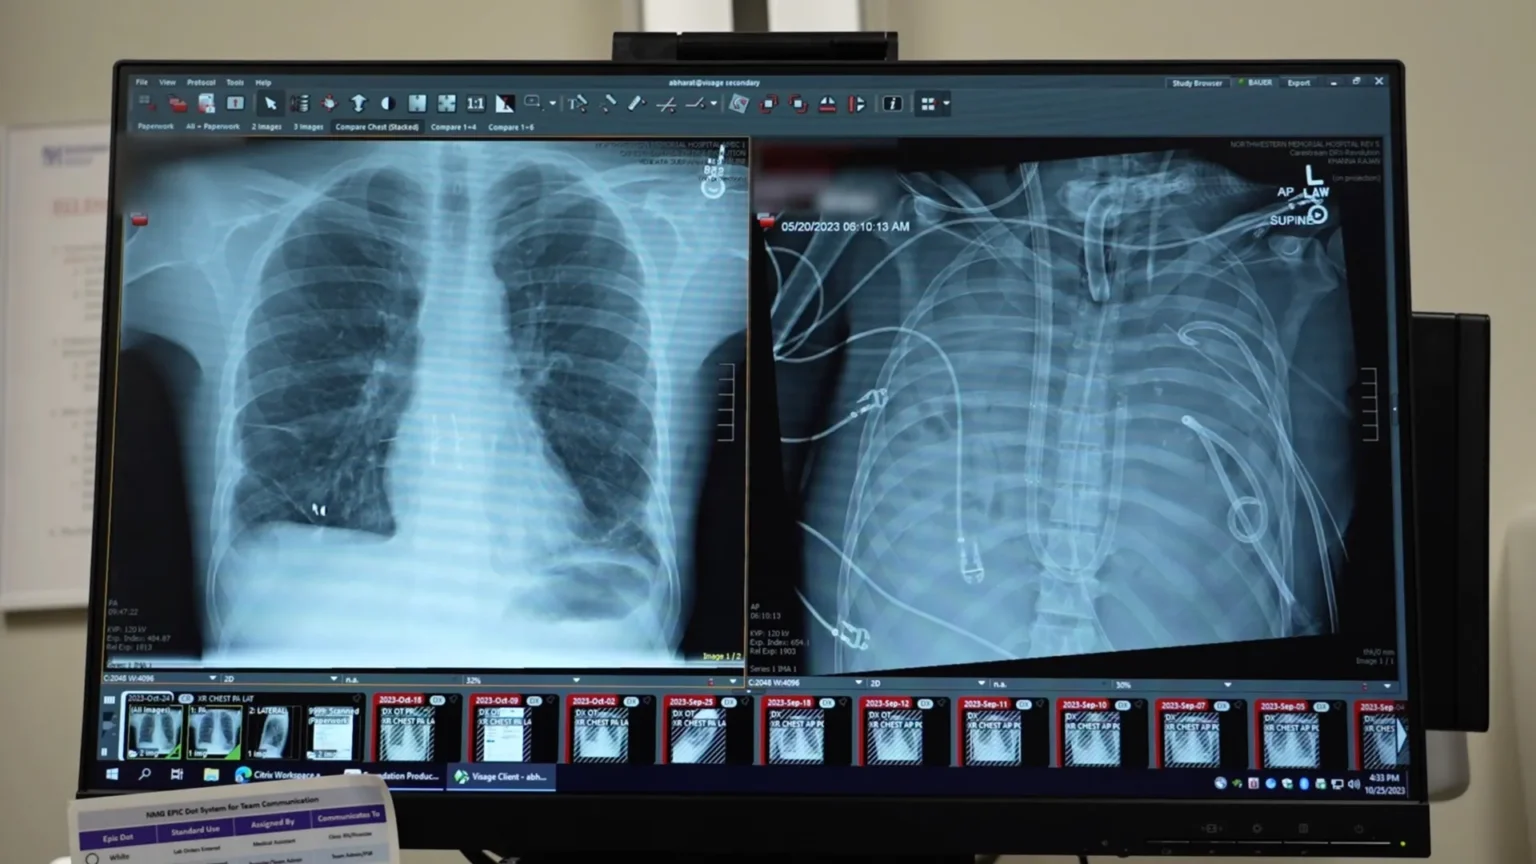

The patient, a 33-year-old man, developed acute respiratory distress syndrome (ARDS), a dangerous condition in which inflammation and infection overwhelm the lungs. His illness started with influenza and quickly worsened to include bacterial pneumonia. As his condition worsened, his lungs, heart, and kidneys began to fail. At that point, a double lung transplant was his only chance of survival.

To address this, medical teams developed an artificial lung system designed to temporarily take over the role of the lungs. This system oxygenated the blood, removed carbon dioxide, and supported circulation, allowing the heart and other organs to continue functioning even when patients had no lungs.

After the damaged lung was removed, the patient’s condition began to improve. Blood pressure stabilized, organs began to recover, and infections were brought under control. Two days later, donor lungs became available and surgeons successfully completed a double lung transplant. Now, more than two years later, the patient maintains healthy lung function and is leading a normal life.